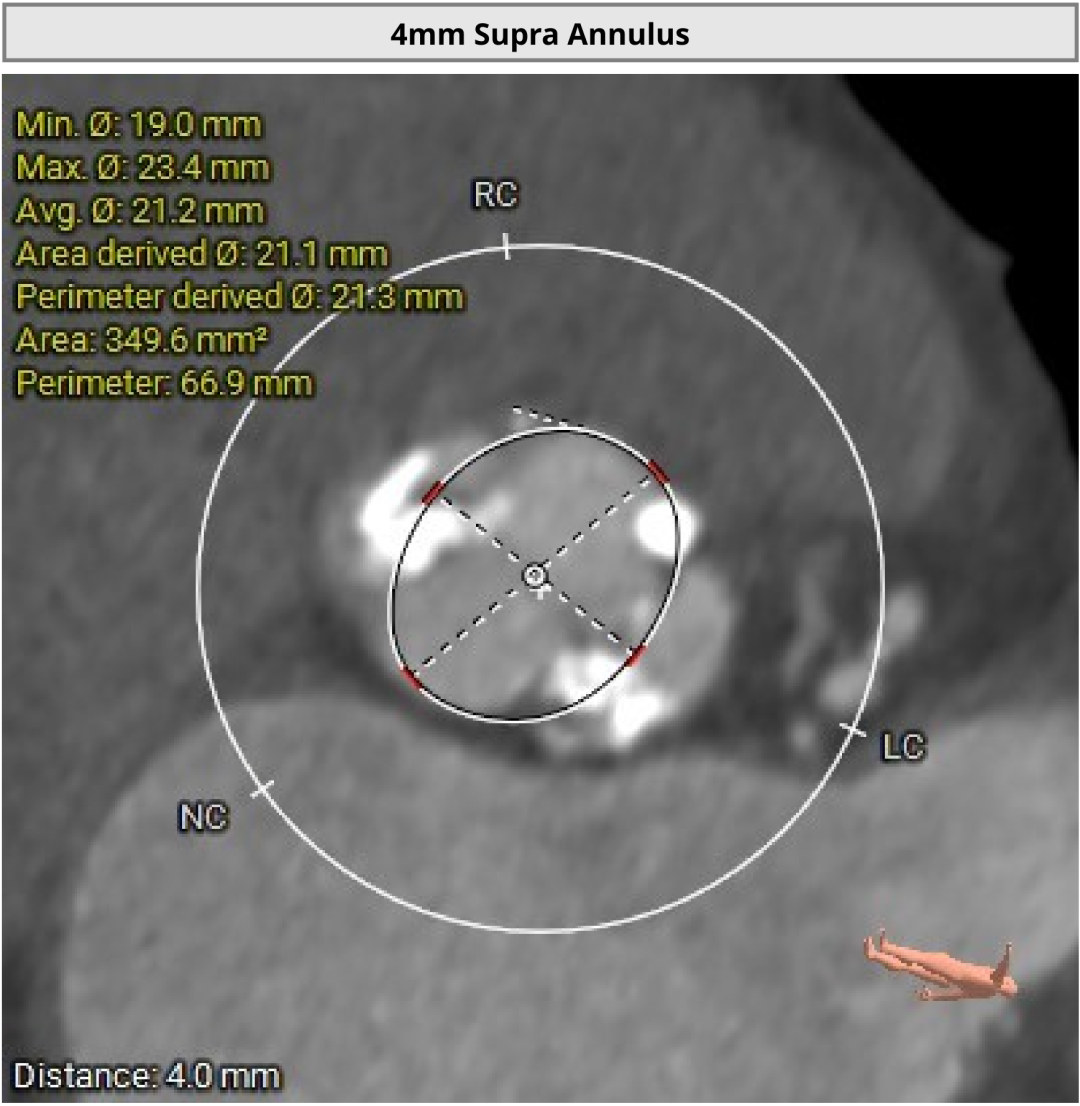

进一步评估显示,患者瓣膜狭窄程度重,瓣叶钙化明显,左心室腔径偏小,手术中对器械通过、瓣膜释放以及循环稳定性的要求都更高。团队结合术前影像和整体身体状况,制定了周密的介入治疗方案,并做好相关风险预案。

CT评估

瓣膜评估